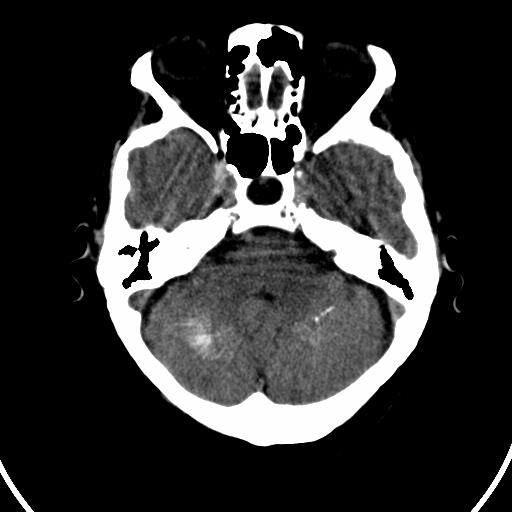

今天碰到的病人,发图上来,大家帮看看该如何诊断?

双侧小脑齿状核钙化,患者是成年人就无病理意义。

双侧小脑齿状核钙化

双侧小脑齿状核钙化,生理性钙化

考虑甲状旁腺功能低下

双侧小脑齿状核钙化 ,原因挺多,有生理性也有病理性的